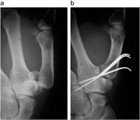

1. 骨折する部位により特徴的な変形を呈する。

1. 関節拘縮を起こさないような内固定と外固定が必要であり、解剖の熟知が重要である。